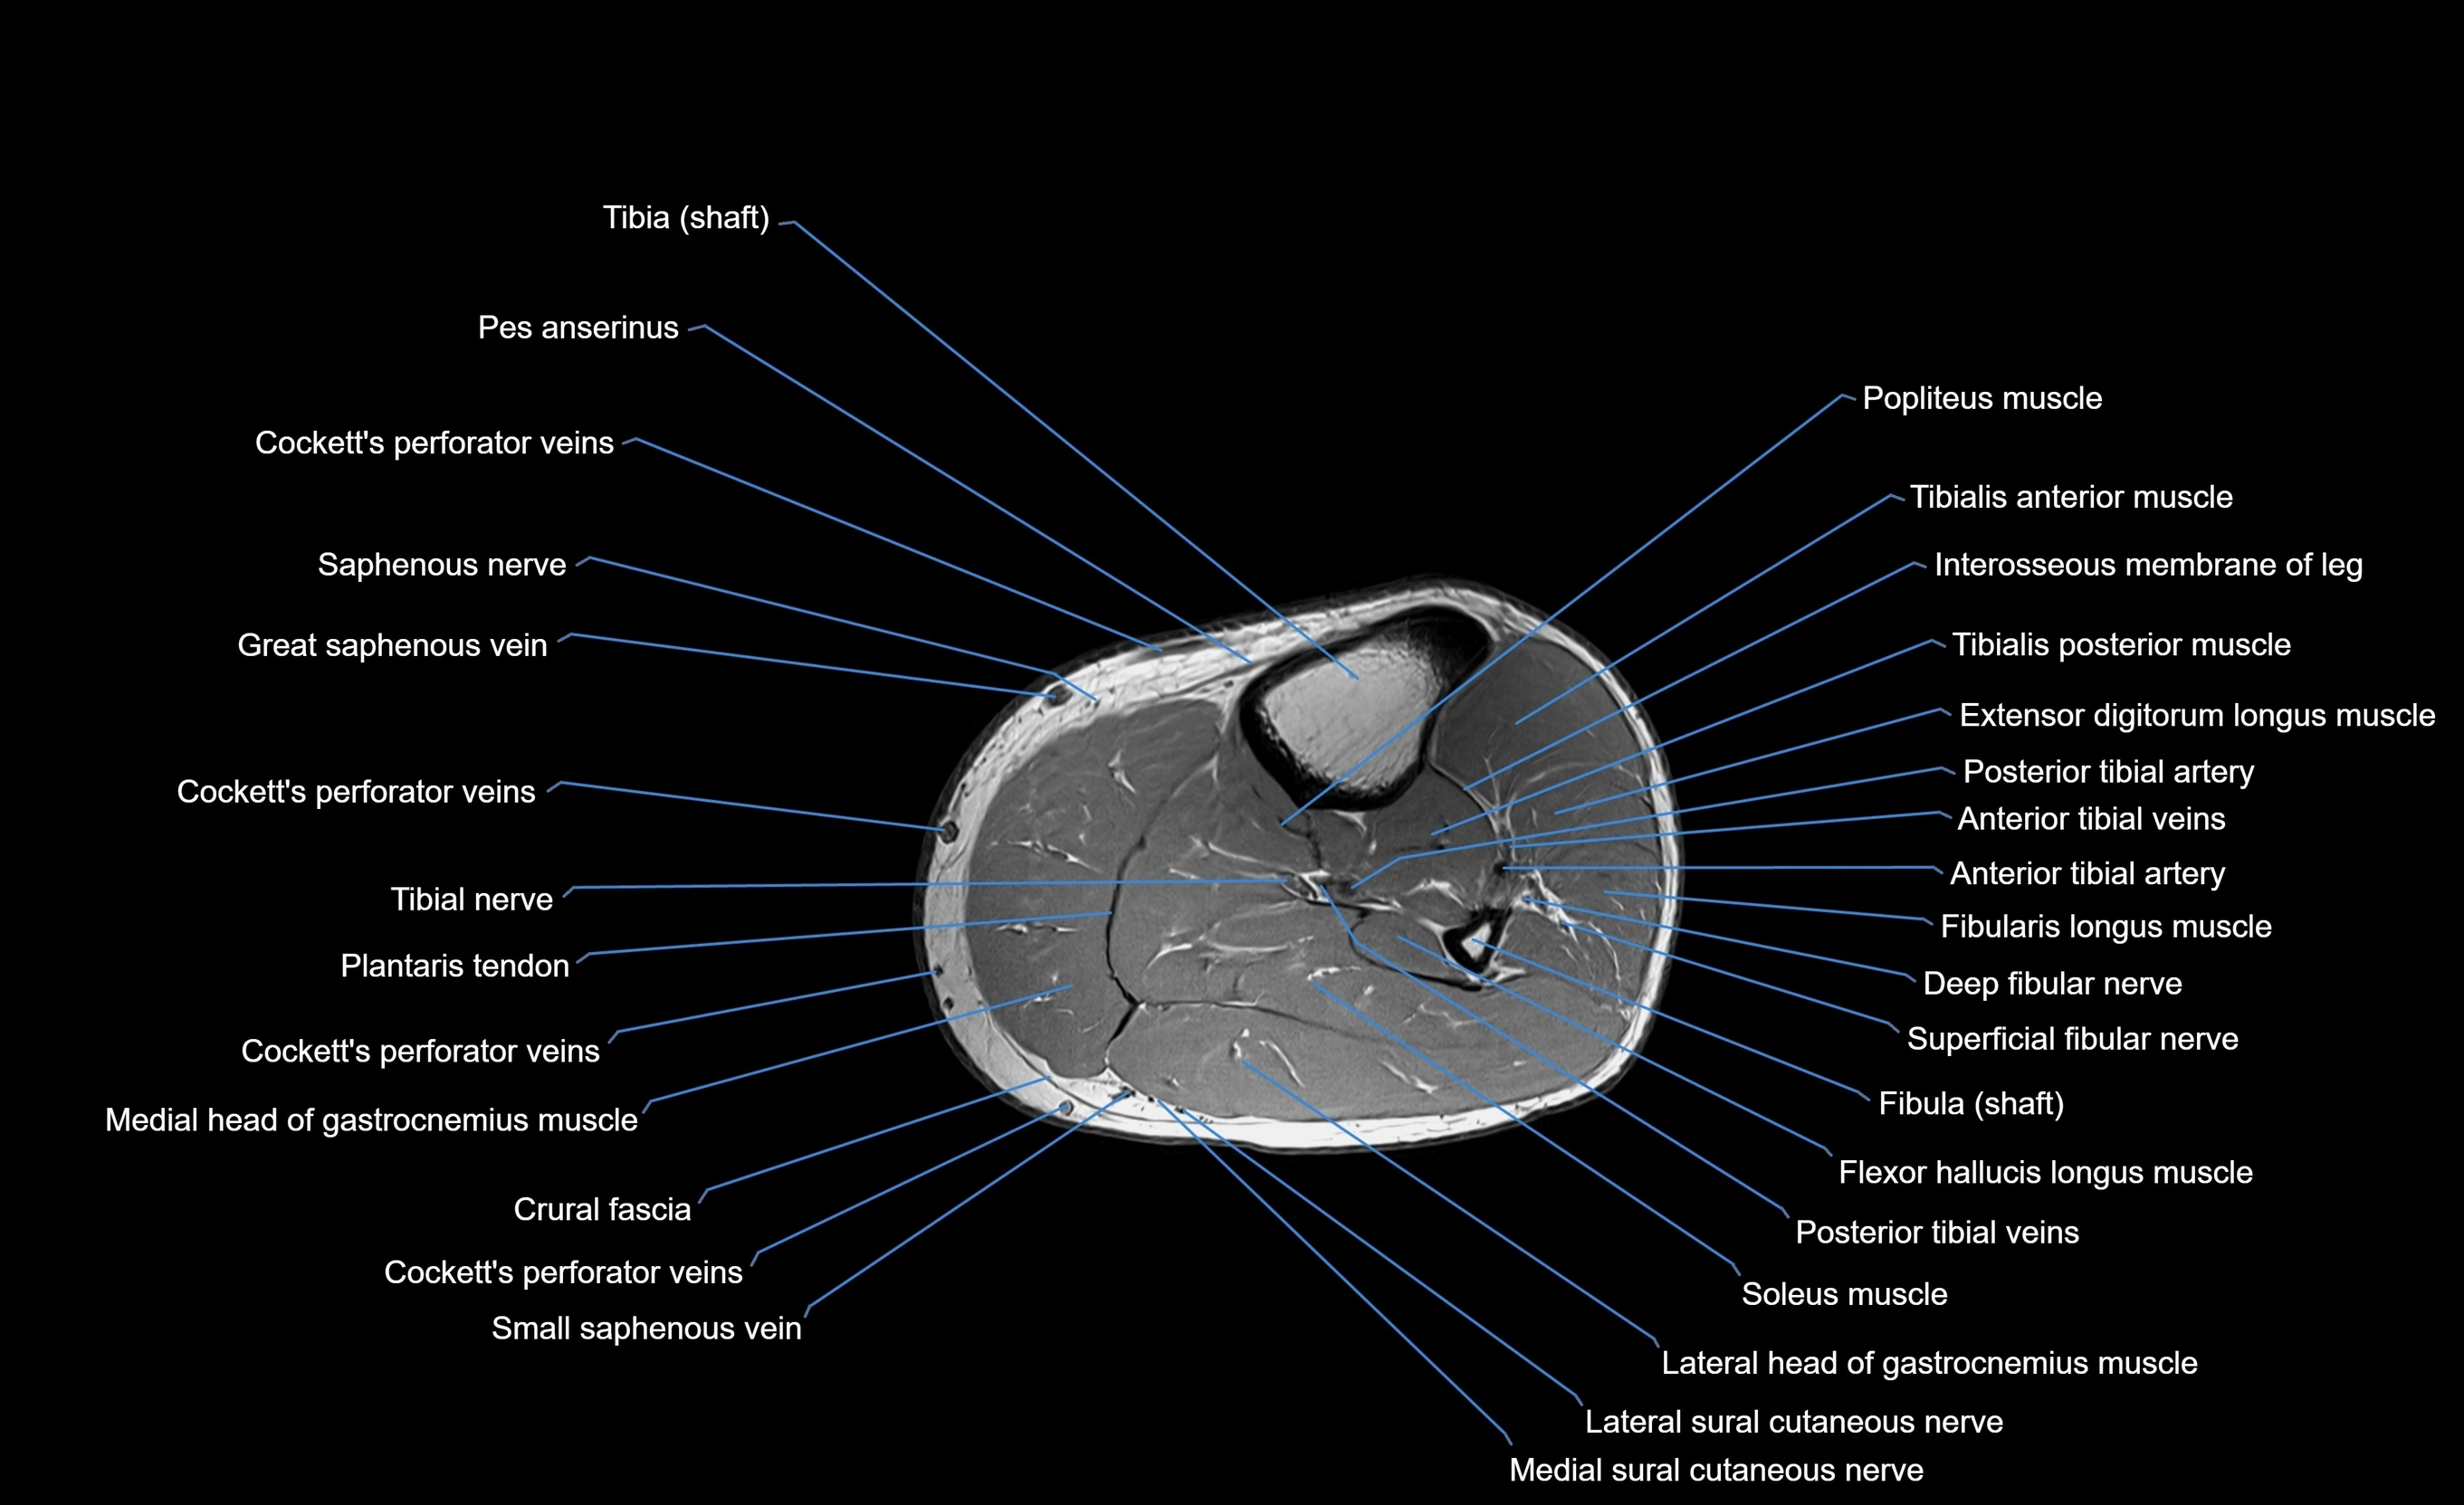

MRI image